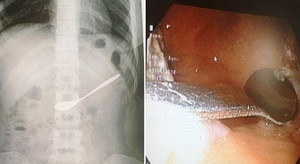

Trong lúc đi uống cà phê với bạn, một cô gái 20 tuổi ở Nghệ An không may nuốt chiếc thìa cà phê vào bụng. Rất may đã được các bác sĩ kịp thời gắp ra khỏi cơ thể an toàn.